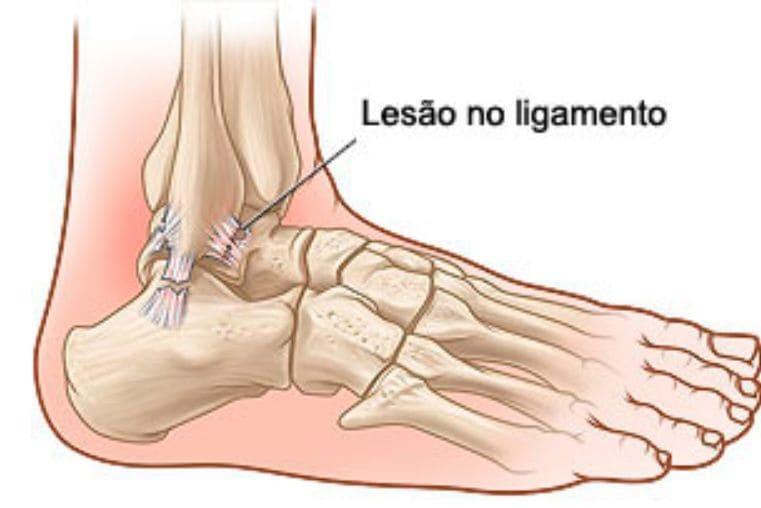

Os sintomas mais comuns são dor ao caminhar ou ao se levantar pela manhã, inchaço, instabilidade no tornozelo, deformidades visíveis nos dedos e dificuldade para realizar atividades rotineiras. Ignorar esses sinais pode levar ao agravamento da condição e a um tratamento mais complexo no futuro.

Um diagnóstico preciso, realizado por um especialista, é crucial para o sucesso do tratamento. A avaliação começa com um exame físico detalhado, analisando a marcha e os pontos de dor. Exames de imagem, como radiografias com carga, ultrassom e ressonância magnética, são fundamentais para avaliar as estruturas ósseas e os tecidos moles.